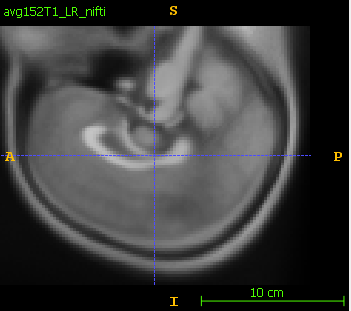

- Open in itk-snap/slicer the original nifti and then the dicom. The dicom is flipped up-down.

- In itk-snap, the original nifti is:

The saved dicom is flipped in S-I axis: